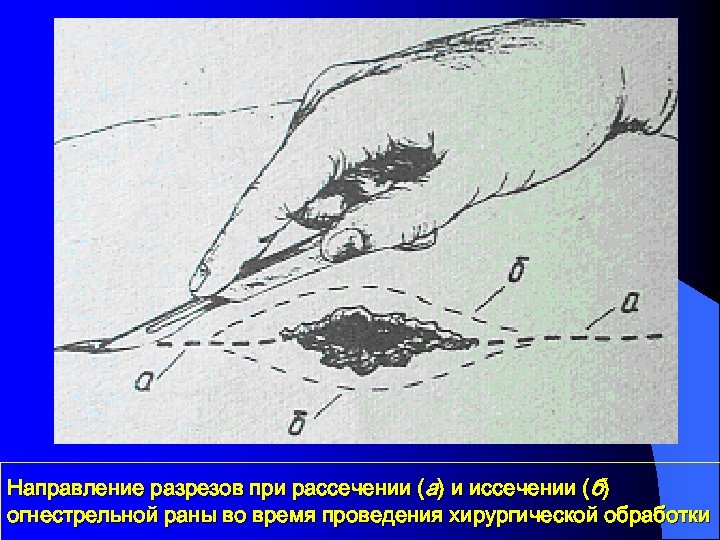

Направление разрезов при рассечении (а) и иссечении (б) огнестрельной раны во время проведения хирургической обработки

Направление разрезов при рассечении (а) и иссечении (б) огнестрельной раны во время проведения хирургической обработки